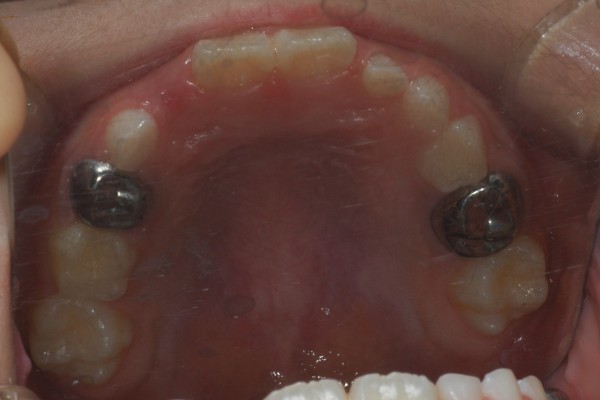

치주염과 충치가 다수 발견돼, 간식은 커녕 음식 섭취도 힘든 상태였습니다.

한 달 동안 총 4회에 걸쳐 충치 부위에 보철물을 씌워 진료를 진행했습니다.